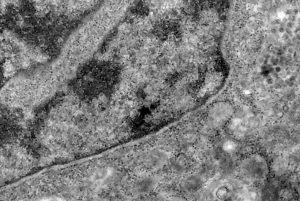

Coronavírus